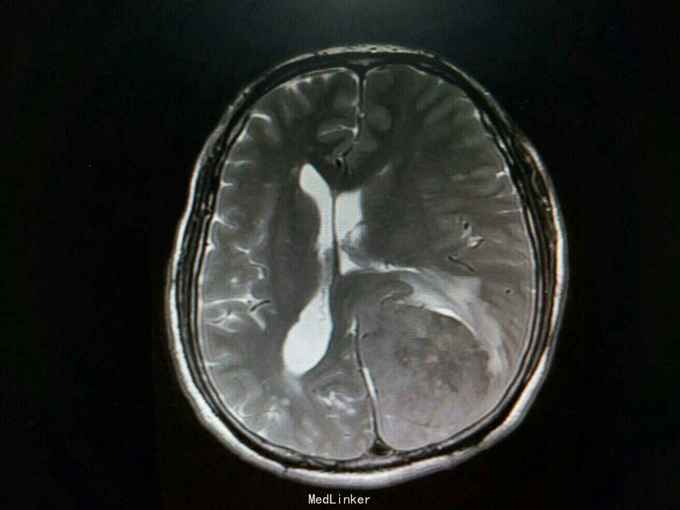

查体:生命体征平稳,神经系统检查未见明显异常。辅助检查:头颅增强+血管MR扫描提示:双侧额顶叶、侧脑室周围见斑片状异常信号区,T1WI呈等信号,T2WI及T2-FLAIR呈稍高信号。左侧枕部大脑镰旁可见团状软组织肿块影,边界清,形态不规则,呈分叶状,大小约62mm×49mm。病灶T1WI呈等信号,T2WI呈稍低信号,周围可见脑脊液环绕;增强扫描病灶明显均匀强化。病灶占位效应较明显,左侧顶枕叶脑实质受压向内移位,左侧侧脑室受压变形。中线结构稍向右移位。余脑实质未见异常信号灶。颅骨未见明确异常。头颅MRA:病灶内可见多发迂曲血管影,可见大脑后动脉及脑膜动脉供血。双侧大脑前、中、后动脉管壁光滑,走行自然,管腔未见明显扩张或狭窄,未见动脉瘤征象。Willis环未见异常。1. 左侧枕部大脑镰旁占位性病变,考虑脑膜瘤可能性大;2. 轻度脑白质疏松;2. 头颅MRA提示病灶血供来自左侧大脑后动脉及脑膜动脉;余未见异常。

诊断:左枕部大脑镰旁脑膜瘤 处理:左枕部开颅大脑镰旁脑膜瘤切除术

术后病理提示:(左顶枕叶肿瘤)脑膜瘤,上皮型,WHOⅠ级。大脑镰旁脑膜瘤是指位于大脑纵裂并与大脑镰相连的一类临床上常见的脑膜瘤,常突入一侧大脑半球内,有时可向双侧发展。也有少数肿瘤呈扁平型,在大脑镰内浸润性生长。肿瘤可由大脑镰脑膜动脉供血,也可由脑内动脉供血,其前部可来自眼动脉分支,后部来自枕动脉,中部可有脑膜中动脉供血。在肿瘤基底和附近的大脑镰内有多条扩张的静脉。